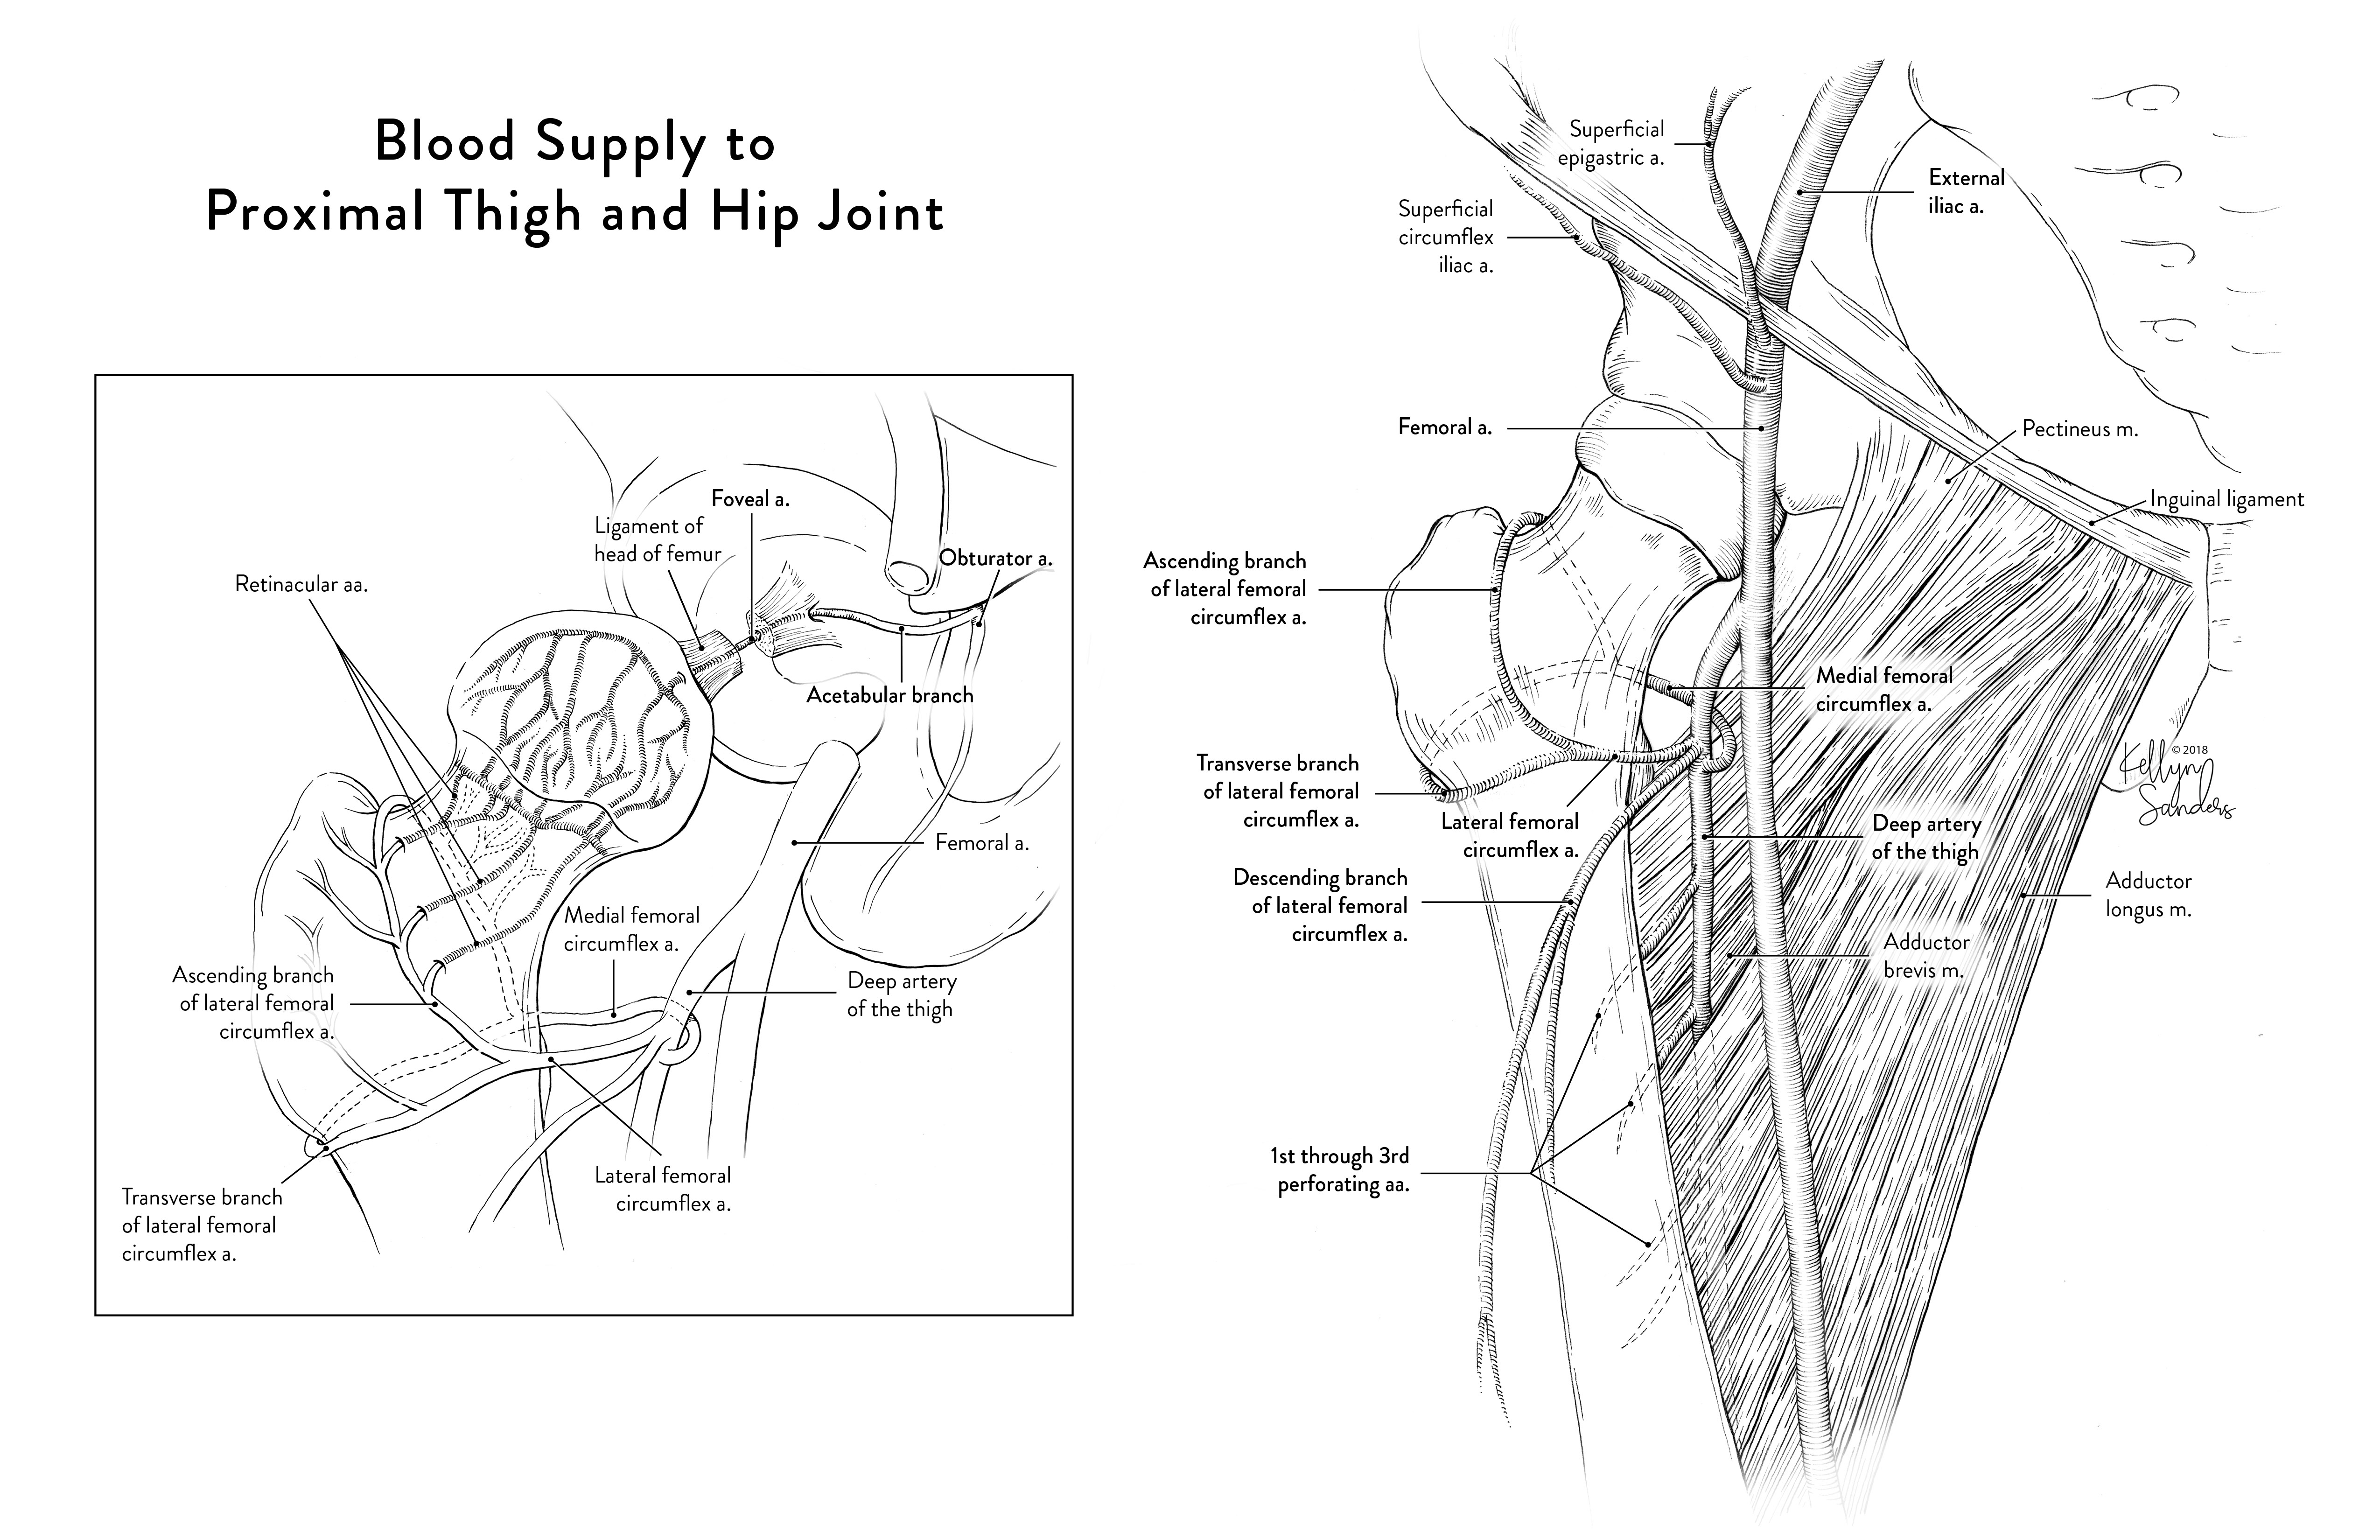

- Anatomy illustration translation from tone

- Anatomy illustration (from cadaver dissection)

Student Artwork